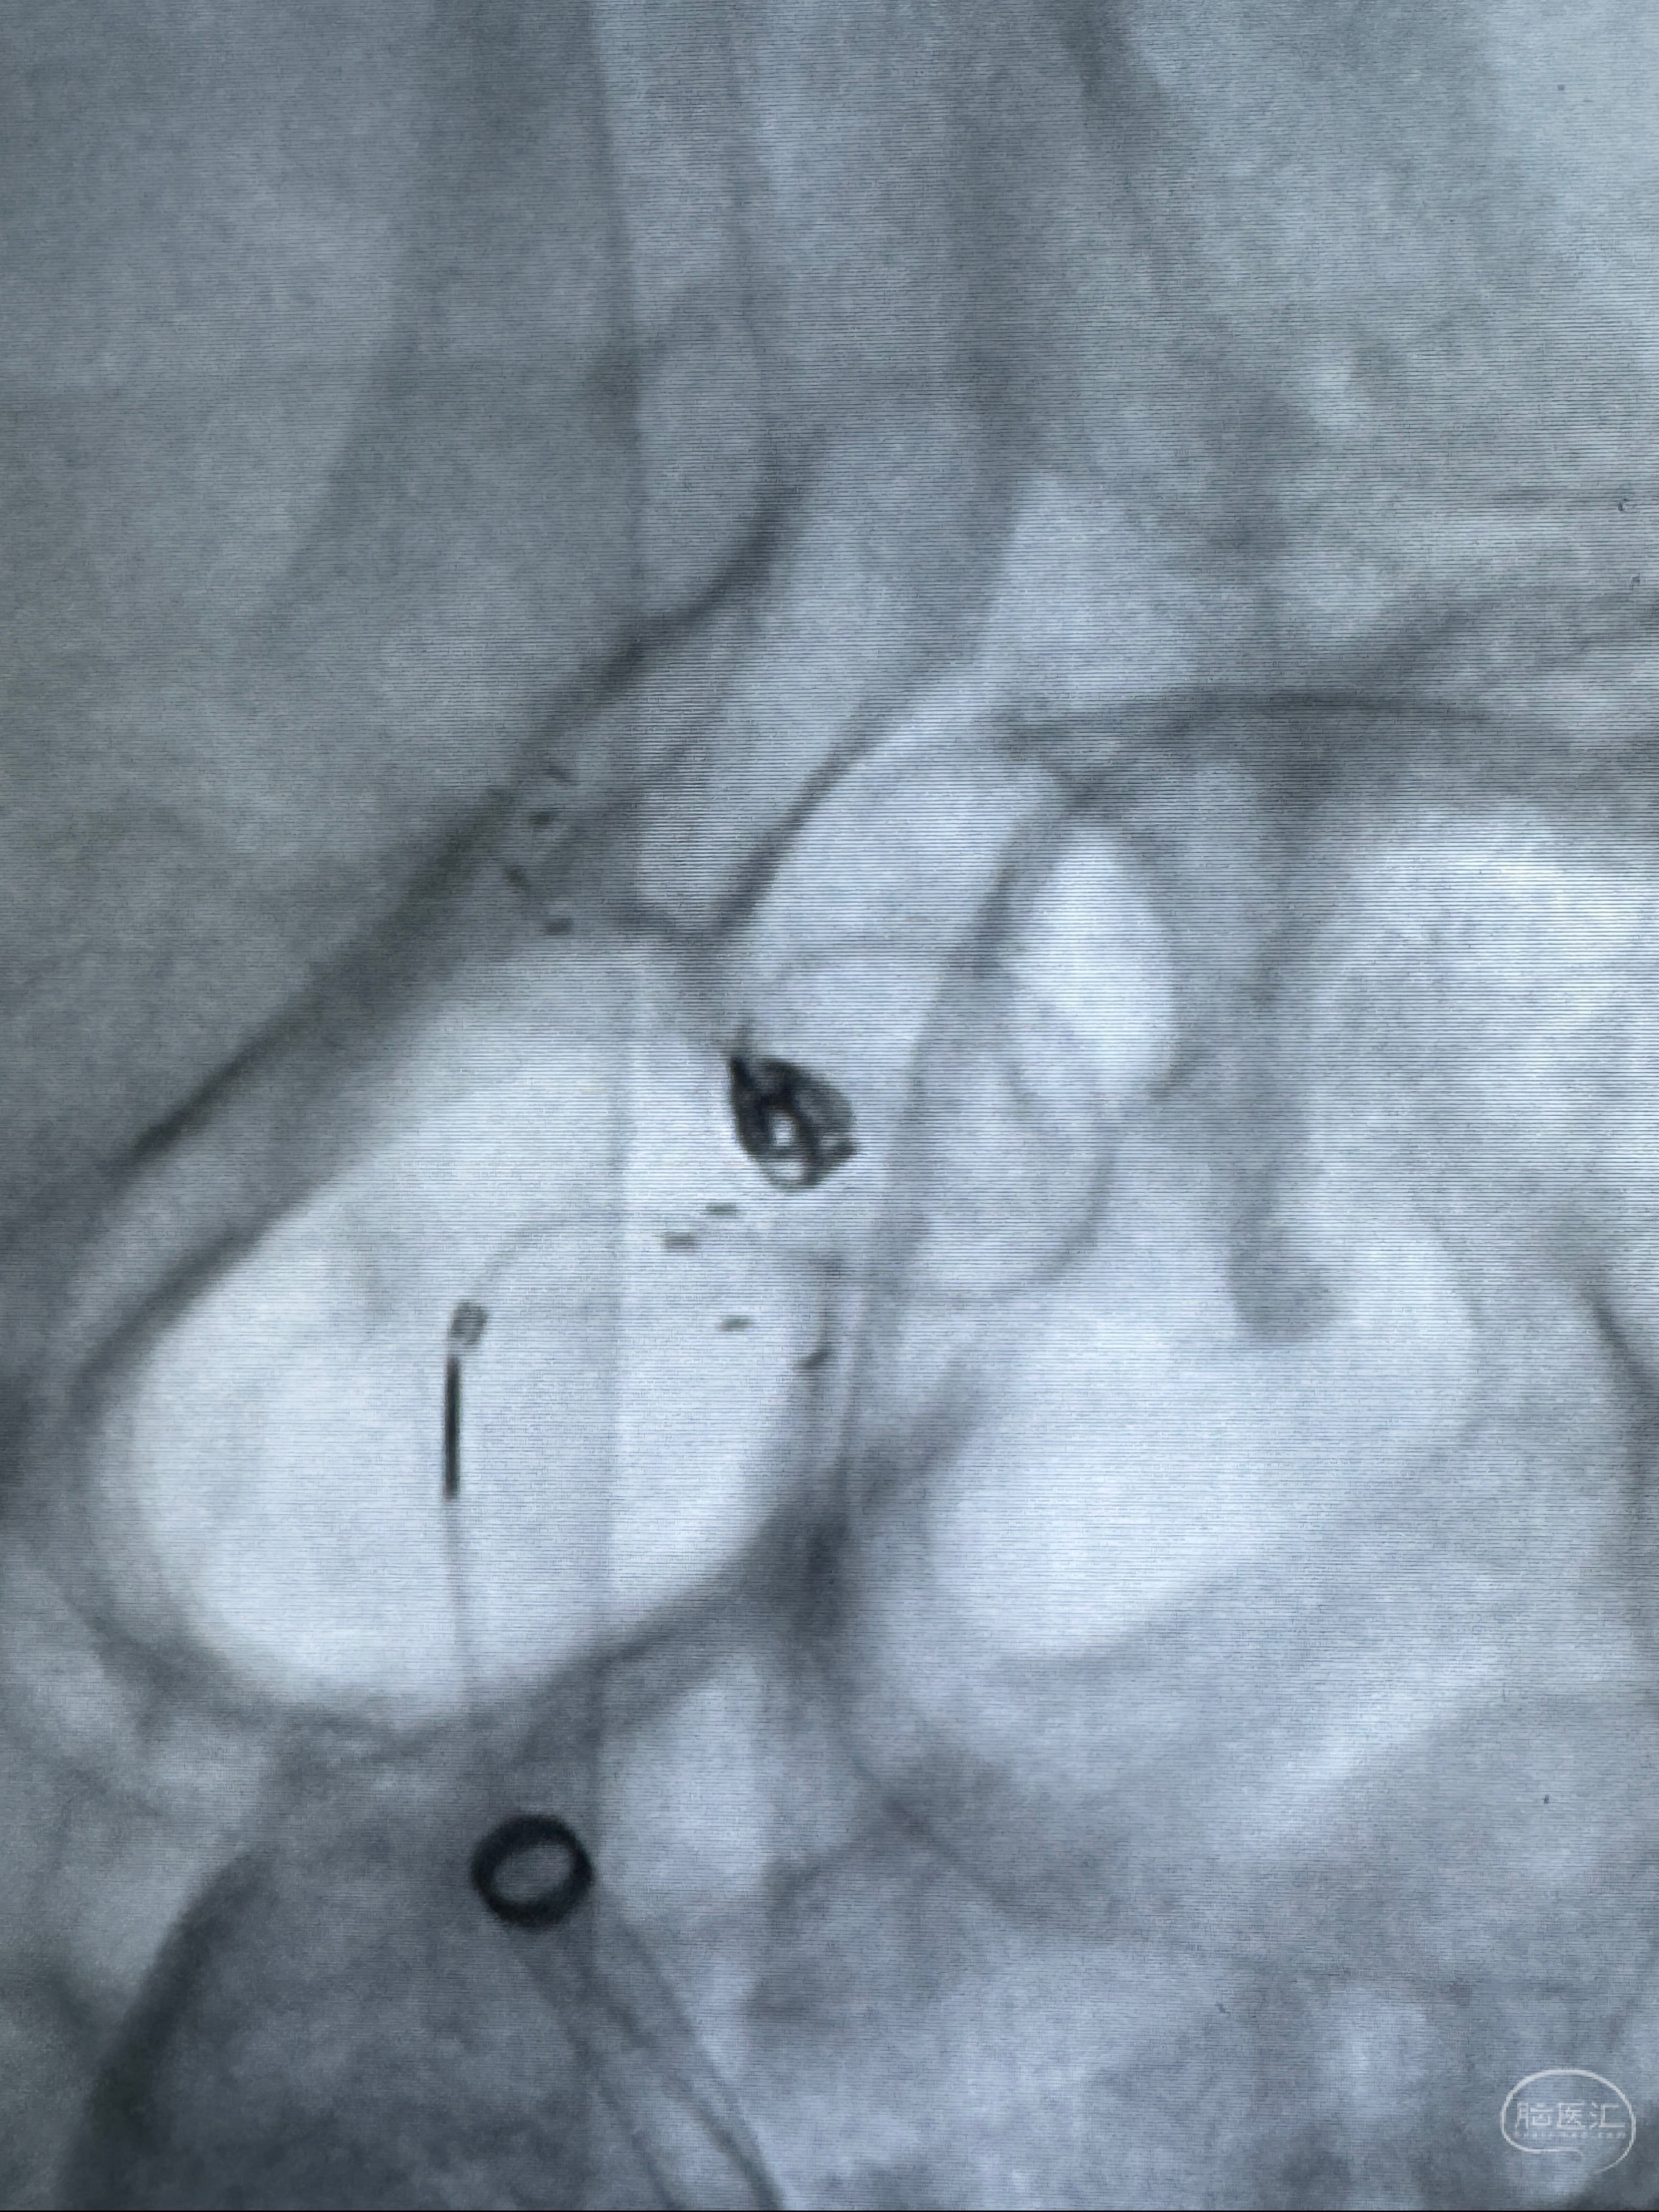

2023-11-13DSA:左侧颈内动脉眼动脉后壁动脉瘤

2023-11-29全麻下行NeuroformEZ4.5-20mm支架辅助栓塞